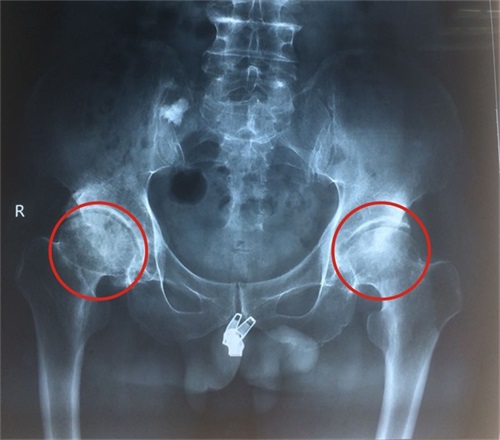

诊断:1.双侧股骨头坏死 2.双髋关节炎(关节僵直)

▲图为术前双侧股骨头坏死的X光片